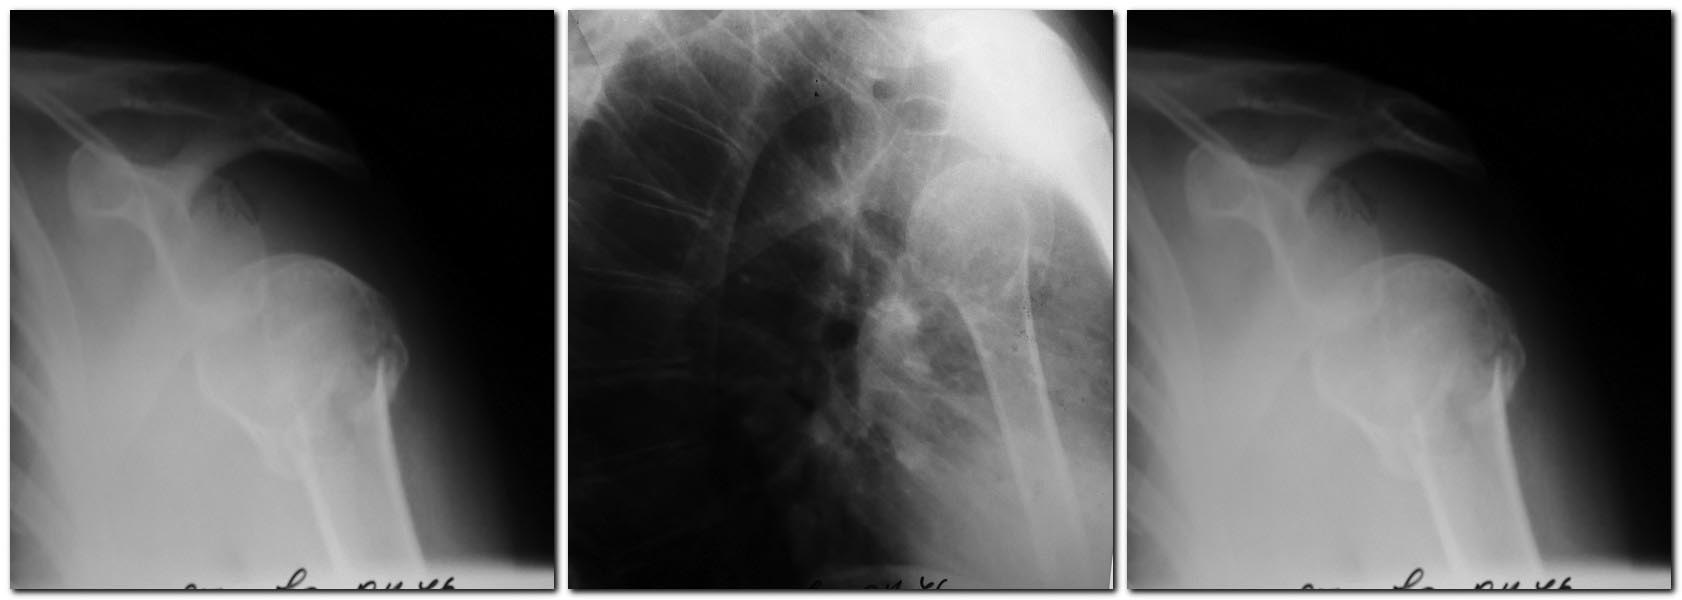

Планирую ревизию надостной мышцы, при ее разрыве -шов. Синтез проксимальным гвоздем( доступна и пластина LCP). Время с момента травмы-2 недели. Правильна ли тактика? Какие подводные камни могут встретиться? Допустима ли трансартикулярная фиксация спицами в случае неустранимого подвывиха? Спасибо.